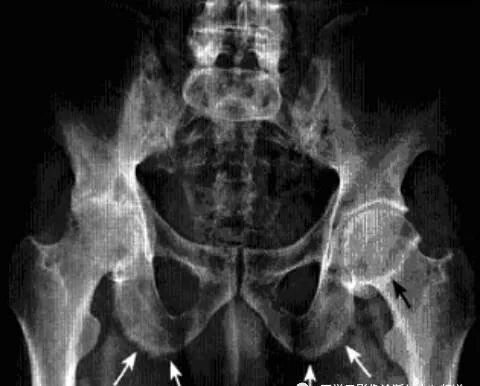

髋关节色素沉着绒毛结节性滑膜炎

一种侵及关节、腱鞘、滑囊或肌腱组织的良性增生伴色素沉着性病变。一般单关节发病,*常累及膝关节,其次是髋关节、踝关节、肩关节、肘关节。

病理:表面凹凸不平,有绒毛状滑膜皱襞覆盖,累及关节囊及周围软组织内血管和神经结构。

临床表现:以20-40岁青年女性多见,多有髋部外伤史,早期无特征,进展缓慢。

影像诊断:早期诊断缺特异性,晚期出现典型骨质破坏。MRI检查具较强特异性及定性诊断作用。